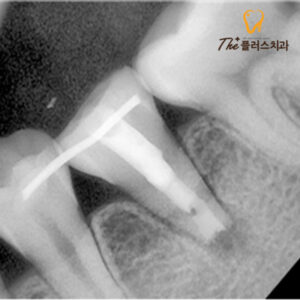

이식한 치아의 경우

다시 자리를 잡는 데 시간이 필요하기 때문에

지속적으로 상태를 확인해 보아야 합니다.

고정을 위해 옆 치아에

스플린트를 달아 고정해 두었고,

시간이 지남에 따라 치아가 고정되어

잘 아문 모습을 볼 수 있었습니다.

환자분께서는 나이가 어렸기 때문에

치아를 보존하는 것이 미래를 생각해서도

좋은 방법이라 정기적으로 잘 내원해 주셨고,

주의 사항도 잘 지켜주셔서

치료를 안정적으로 마무리하였습니다.